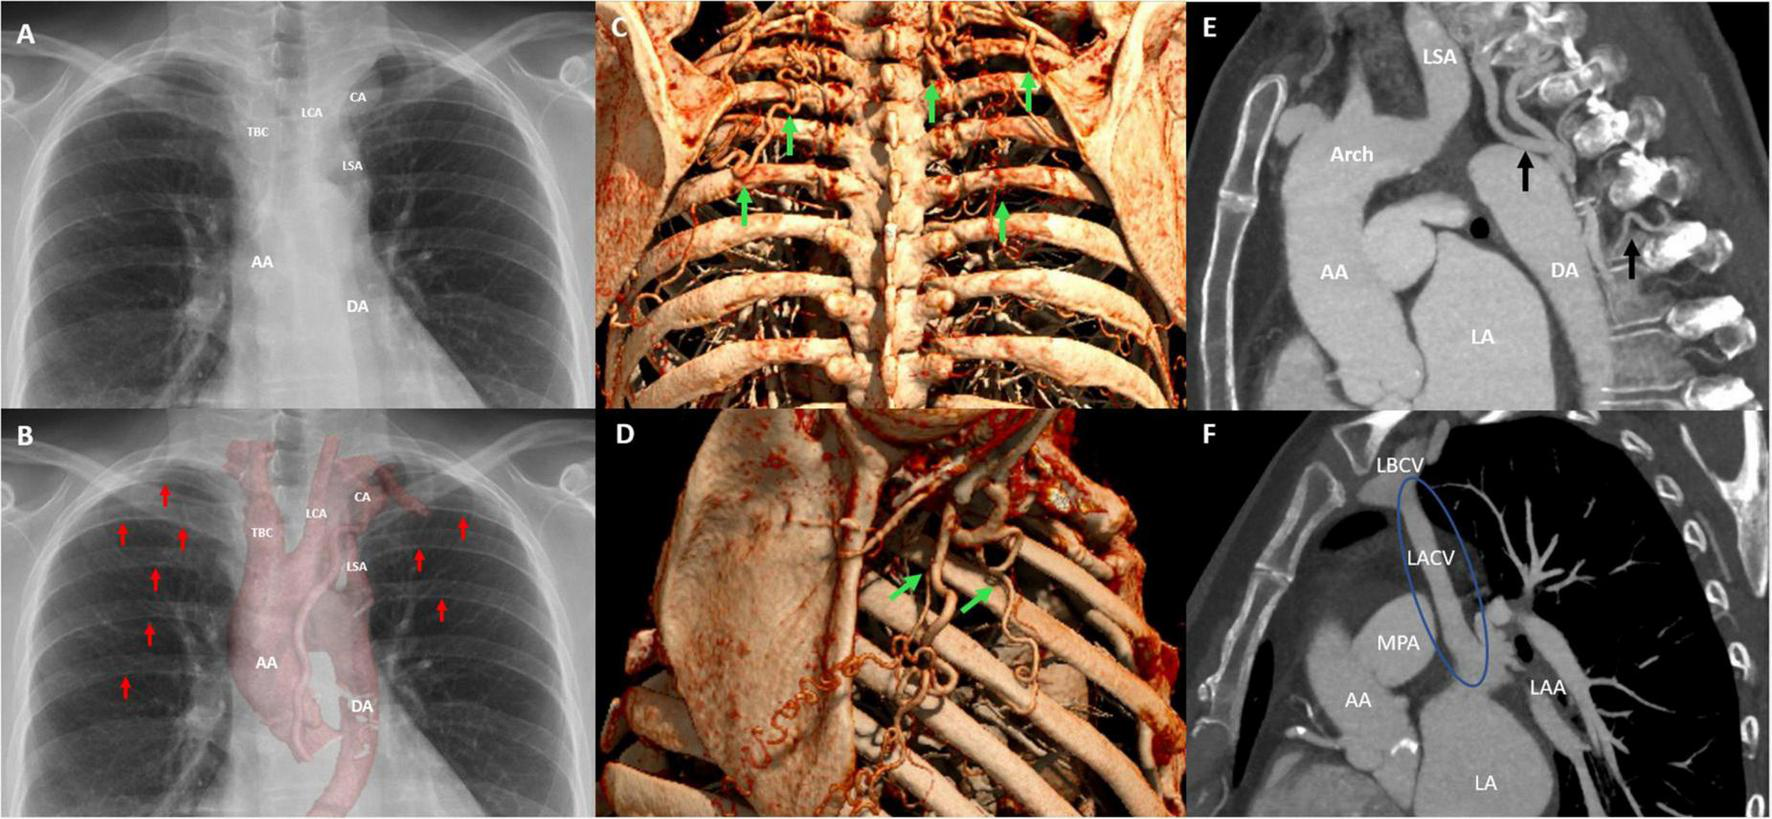

FIGURE 2

Postero-anterior chest radiograph illustrates the aneurysmatic collateral artery projecting over the apical–medial aspect left upper lobe and mediastinal silhouette (A). In addition, the postero-anterior chest radiograph with multifocal rib notching (red arrows) and projection of the cinematic 3D-reconstruction of the thoracic aorta illustrating the CoA and associated aneurysmatic collateral artery (B). Oblique sagittally reformatted maximum intensity projection (MIP) cinematic 3D-rendering of thoracic CTA shows hypertrophic collateral arteries posterior (C) and lateral (D) alongside the chest wall, indicated by green arrows. The sagittal CTA image illustrating collateral arteries and hypertrophic intercostal arteries inserting into the descending aorta (E), and the levoartriocardinal vein (F). AA, ascending aorta; DA, descending aorta; CA, aneurysmatic collateral artery; LSA, left subclavian artery; LCA, left carotid artery; TBC, truncus brachiocephalicus; Arch, aortic arch; LSA, left subclavian artery; LA, left atrium; LACV, levoatriocardinal vein; LBCV, left brachiocephalic vein.

A CTA of the chest was performed to accurately visualize the anatomy of the thoracic aorta. This confirmed a severe, pin-point coarctation with a minimal double-oblique diameter of 4 × 4 mm just distal to the origin of the left subclavian artery. Furthermore, CTA revealed hypertrophic intercostal, internal mammary, and scapular arteries (Figures 2C–E), a levoatriocardinal vein (LACV) connecting the truncus brachiocephalicus with the left atrium (Figure 2F), and an extensive intrathoracic collateral network with a large paravertebral aneurysm (29 × 24 × 24 mm) of one of the collateral arteries arising from the left subclavian artery (Figures 3A, C, E). In addition, a high multi-vessel coronary plaque burden, including a significant proximal left anterior descending lesion, was documented. Given persistent hypertension, treatment with a dihydropyridine calcium channel blocker (amlodipine) and an angiotensin-converting enzyme inhibitor (lisinopril) was initiated.

Clinical work-up for a complicated bacteriemia, as well as the abnormalities on physical examination, prompted further evaluation. Transthoracic echocardiography showed a concentric hypertrophic left ventricle (LV) with an increased LV mass index (143 g/m2) with a good systolic function (LVEF 59%) and a functionally bicuspid aortic valve with moderate regurgitation and a mobile mass of 4 mm in length on the non-coronary cusp. Moreover, mild dilation of the ascending aorta (38 mm) and narrowing of the aorta distal from the origin of the left subclavian artery with the antegrade diastolic flow in the thoracic aorta with a typical “saw tooth” pattern and an estimated pressure gradient of 78 mmHg (Vmax 4.4 m/s) was observed, indicating significant aortic coarctation (Figures 1A–G). The ECG showed sinus rhythm with high voltages of the QRS complex in left precordial leads, meeting the Sokolow–Lyon criteria for left-ventricular hypertrophy. A chest X-ray showed subtle bilateral notching on the inferior borders of several posterior ribs and a rounded opacity projecting over the paramediastinal aspect of the left upper lobe (Figures 2A, B). Given the good response to antibiotic treatment, the small size of the vegetation (<10 mm), no signs of distal embolization, and non-severe aortic valve regurgitation which was hemodynamically well tolerated, conservative antibiotic treatment with intravenous benzylpenicillin for a total of 6 weeks was pursued after multidisciplinary evaluation by the endocarditis team (20–22). Blood cultures taken a day after antibiotic treatment initiation showed no growth, and the patient remained afebrile. After antibiotic treatment, the patient showed no signs of persistent or recurrent infection, and blood cultures 4 months following the last dose of benzylpenicillin remained negative.